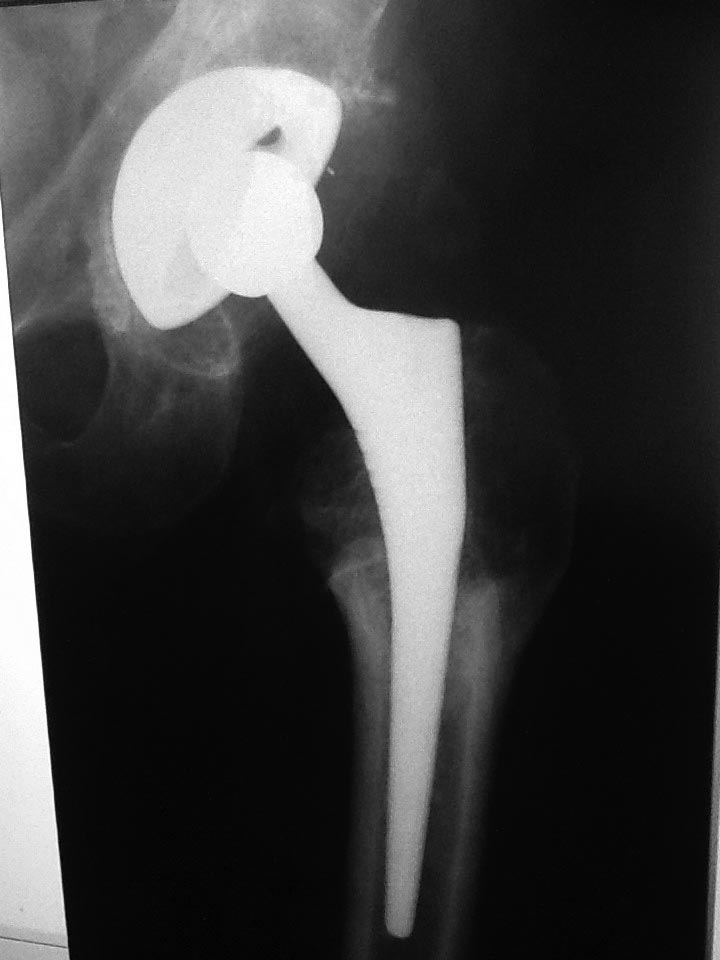

Уважаемые коллеги помогите определиться с тактикой Пациент 60-ти лет около двух лет назад выполнено тотальное б/цементное эндопротезирование по поводу двухстроннего коксартроза, состояния после остеотомий проксимальных отделов бедренных костей. Послеоперационный период спокойный. Больной появлялся на контрольные осмотры в 2, 6, 12 мес, 2 года. На протяжении всего времени отмечает выраженный болевой синдром в области оперированного бедра, передвигается при помощи костылей. Обследован у невролога, уровень С реактивного протеина и лейкоформула в пределах нормы, отечности на бедре нет. Учитывая измененный проксимальный отдел бедра и как следствие интраоперационные трудности обращает на себя внимание передне-заднее расположение ножки эндопротеза (конфликт с задним кортикалом) Может ли такое положение компонента быть причиной болевого синдрома? Поможет ли ревизионное вмешательство по удалению ножки и корректная установка компонента?

прямая проекция

Уважаемый Игорь, Р-граммы не очень качественные, но если исключить неврологию, тенопатию (а это достаточно четкая клиническая картина), то складывается впечатление о нестабильности бедренного компонента. Само положение спереди назад с упором в кортикал не критично, в этом случае беспокоят боли в бедре после физической нагрузки, кость реагирует периостальным утолщением и по мере компенсаторного увеличения костной массы боль уменьшается. Но в Вашем случае смущает плохое заполнение канала в проекции дистальной части ножки на АР рентгенограммах, фиксация только на уровне остеотомии, а этого может быть недостаточно. И вообще непонятно, насколько хорошо ножка фиксирована в проксимальной части. Целесообразно сделать полипозиционные снимки. Болевой синдром столь длительной продолжительности при отсутствии других причин служит основанием для ревизии с установкой конической ножки типа Вагнера с четкой ориентацией по каналу.